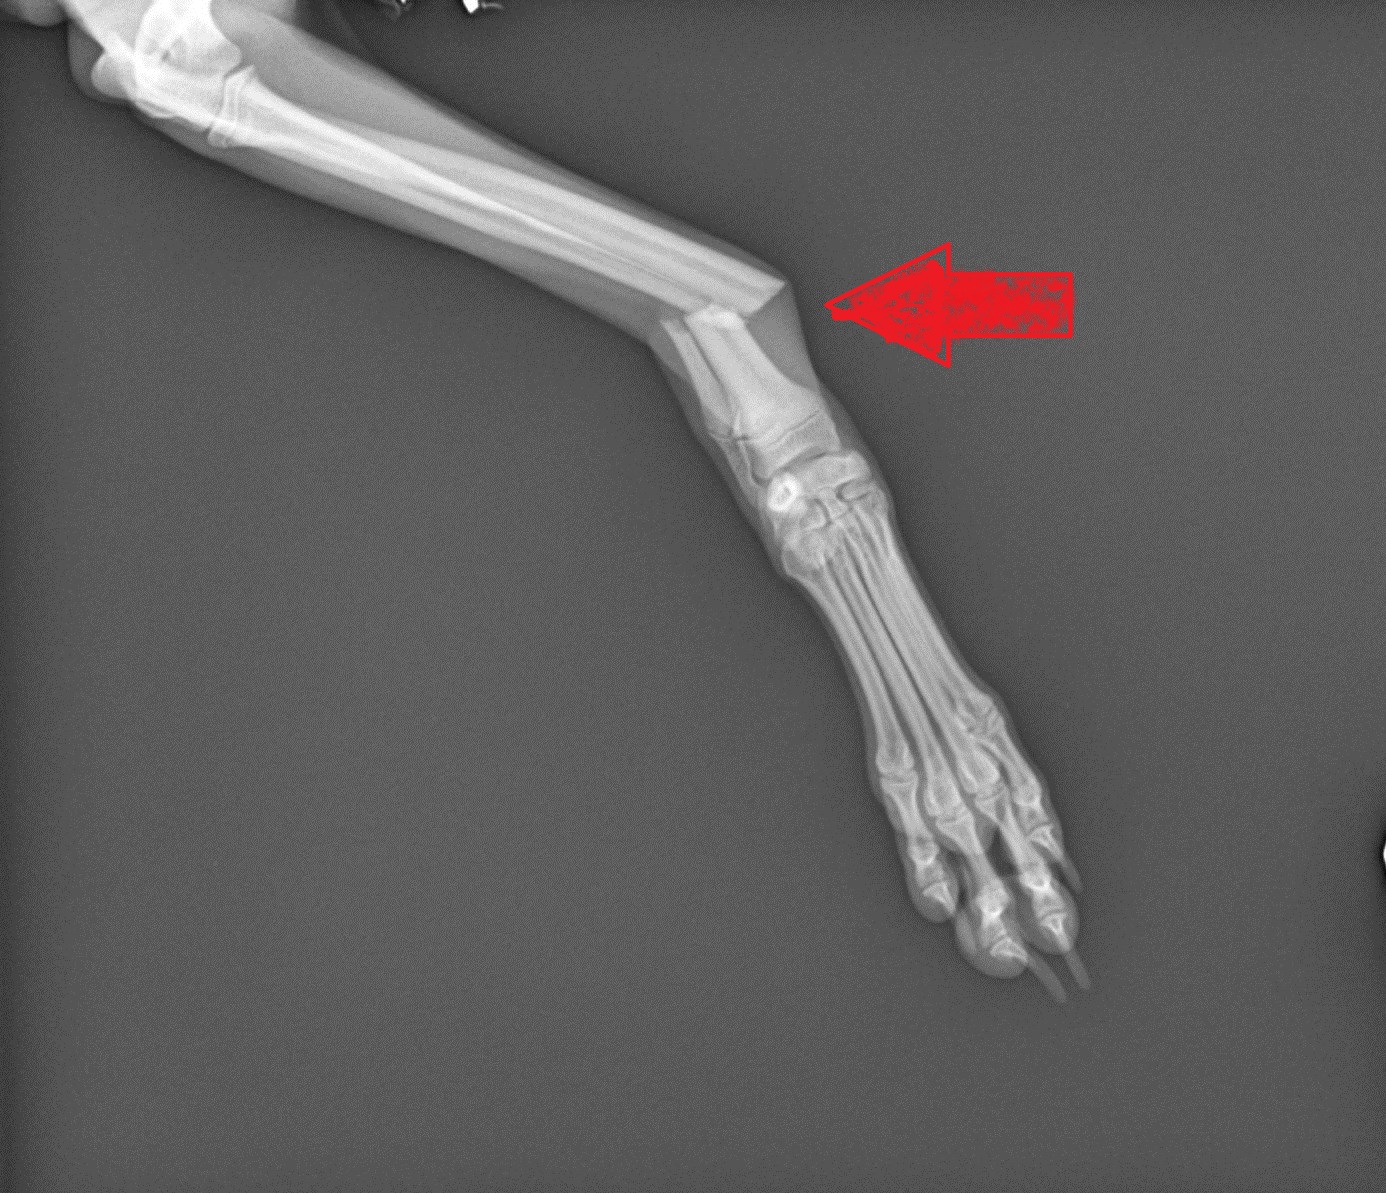

2. Limping

Yet 99% of the time, LIMPING = PAIN.

If your pet holds the leg up, it’s because they know that if they put weight on it, it’s going to hurt. So they learn, and they limp or hold the leg up to stop the pain.

In our practice, the most common reason for limping in a back leg is a torn ACL.